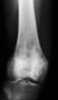

Mixed sclerotic bone dysplasia

Paget's disease of bone (commonly known as Paget's disease or, historically, osteitis deformans) is a condition involving cellular remodeling and deformity of one or more bones. The affected bones show signs of dysregulated bone remodeling at the microscopic level, specifically excessive bone breakdown and subsequent disorganized new bone formation. [Source: Wikipedia ]